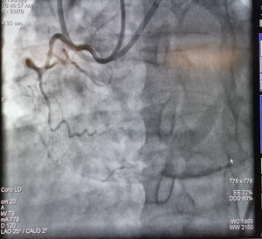

CTO开通前影像 CTO开通后影像